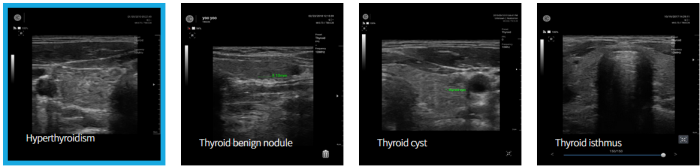

Handheld Ultrasound Devices for Clinical Value - Thyroid - Medical / Health Care

Hyperthyroidism.